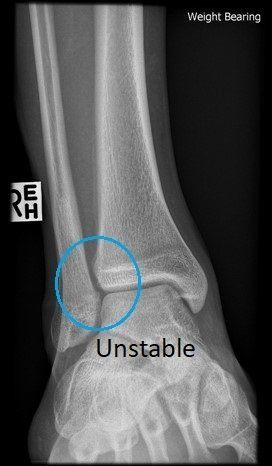

Weight-bearing X-rays comparing both ankles are useful, with MRI, weight-bearing CT and even ankle arthroscopy sometimes required to determine whether the syndesmosis is stable or unstable (see images below).